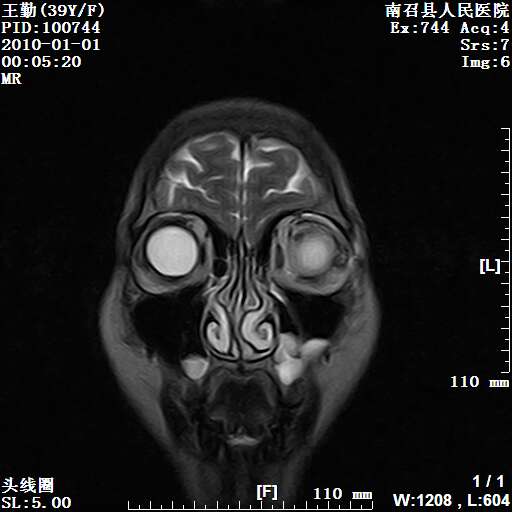

以下是引用随光逐影在2010-1-22 9:03:00的发言:[br]考虑左侧中颅窝(蝶骨翼区)脑膜瘤侵犯蝶骨翼并突入左侧眼眶。

以下是引用水过无痕在2010-1-22 14:55:00的发言:[br]一、定位:颅外占位;二、定性:恶性可能性大;三、组织来源:来源于左侧眼外直肌或其他部位;考虑为:横纹肌肉瘤>转移瘤>脑膜瘤.